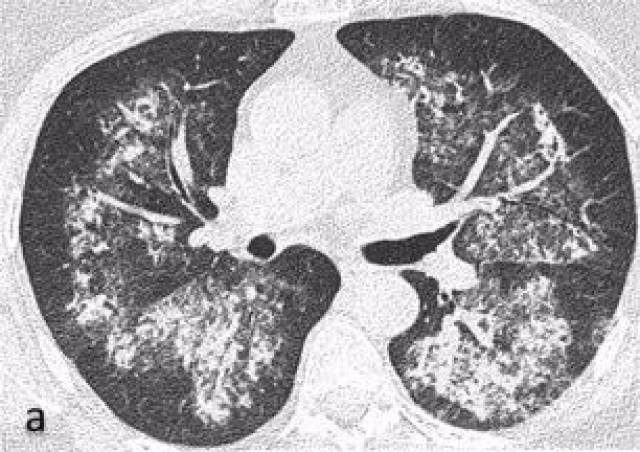

肉芽肿性血管炎合并弥漫性肺泡出血一例